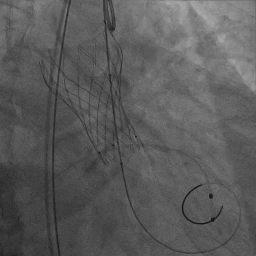

患者取平卧位,局麻镇静,颈内静脉置入中心静脉置管,测中心静脉压3cmH2O,左侧桡动脉穿刺置管监测动脉压力。术区无菌消毒铺巾,穿刺右侧桡动脉并置入6F鞘管,超声引导下穿刺双侧股动静脉,右股动脉预置两把Proglide缝合器,左侧股动静脉留置6F鞘管。将Lunderquist加硬导丝送至升主动脉,沿加硬导丝送20F GORE动脉鞘管。将临时起搏漂浮电极经右股静脉送至右室心尖部位,测试起搏器工作良好。予肝素6000单位,ACT大于250s。经左股动脉置入6F猪尾导管,在释放体位下行主动脉根部造影。经右侧桡动脉送脑保护装置分别在左颈总动脉、头臂干动脉释放保护。经右侧股动脉送入6F JL4.0造影导管造影提示:左前降支未见明显狭窄,TIMI血流III级;回旋支未见明显狭窄,TIMI血流III级。送入6F JR4.0造影导管造影提示:右侧冠脉未见明显狭窄,TIMI血流III级。在AL2导管指引下,直头导丝跨瓣至左心室,沿导丝送猪尾导管至左心室,测得跨瓣压差50mmHg。经猪尾导管送入塑形后的加硬导丝送至左心室内,沿加硬导丝送启明L26主动脉瓣系统至主动脉瓣处,在释放体位下释放至工作状态,经猪尾导管行主动脉造影示瓣膜定位良好。继续完全缓慢释放瓣膜。送入20×40mm球囊至主动脉瓣,在180次/分起搏下,收缩压下降至50mmHg时行球囊扩张,扩张无明显腰征。主动脉造影示瓣膜支架膨胀良好,微量瓣周漏。撤出输送系统。经胸超声评估主动脉瓣位为人工瓣回声,位置固定,瓣叶活动良好。主动脉造影提示主动脉无夹层、出血。行造影提示腹主动脉、髂动脉、股总动脉未见明显异常,缓慢撤出20F大鞘管,缝合右侧股动脉穿刺点,保留右侧临时起搏器并固定良好。

工作体位瓣膜释放

瓣膜完全释放